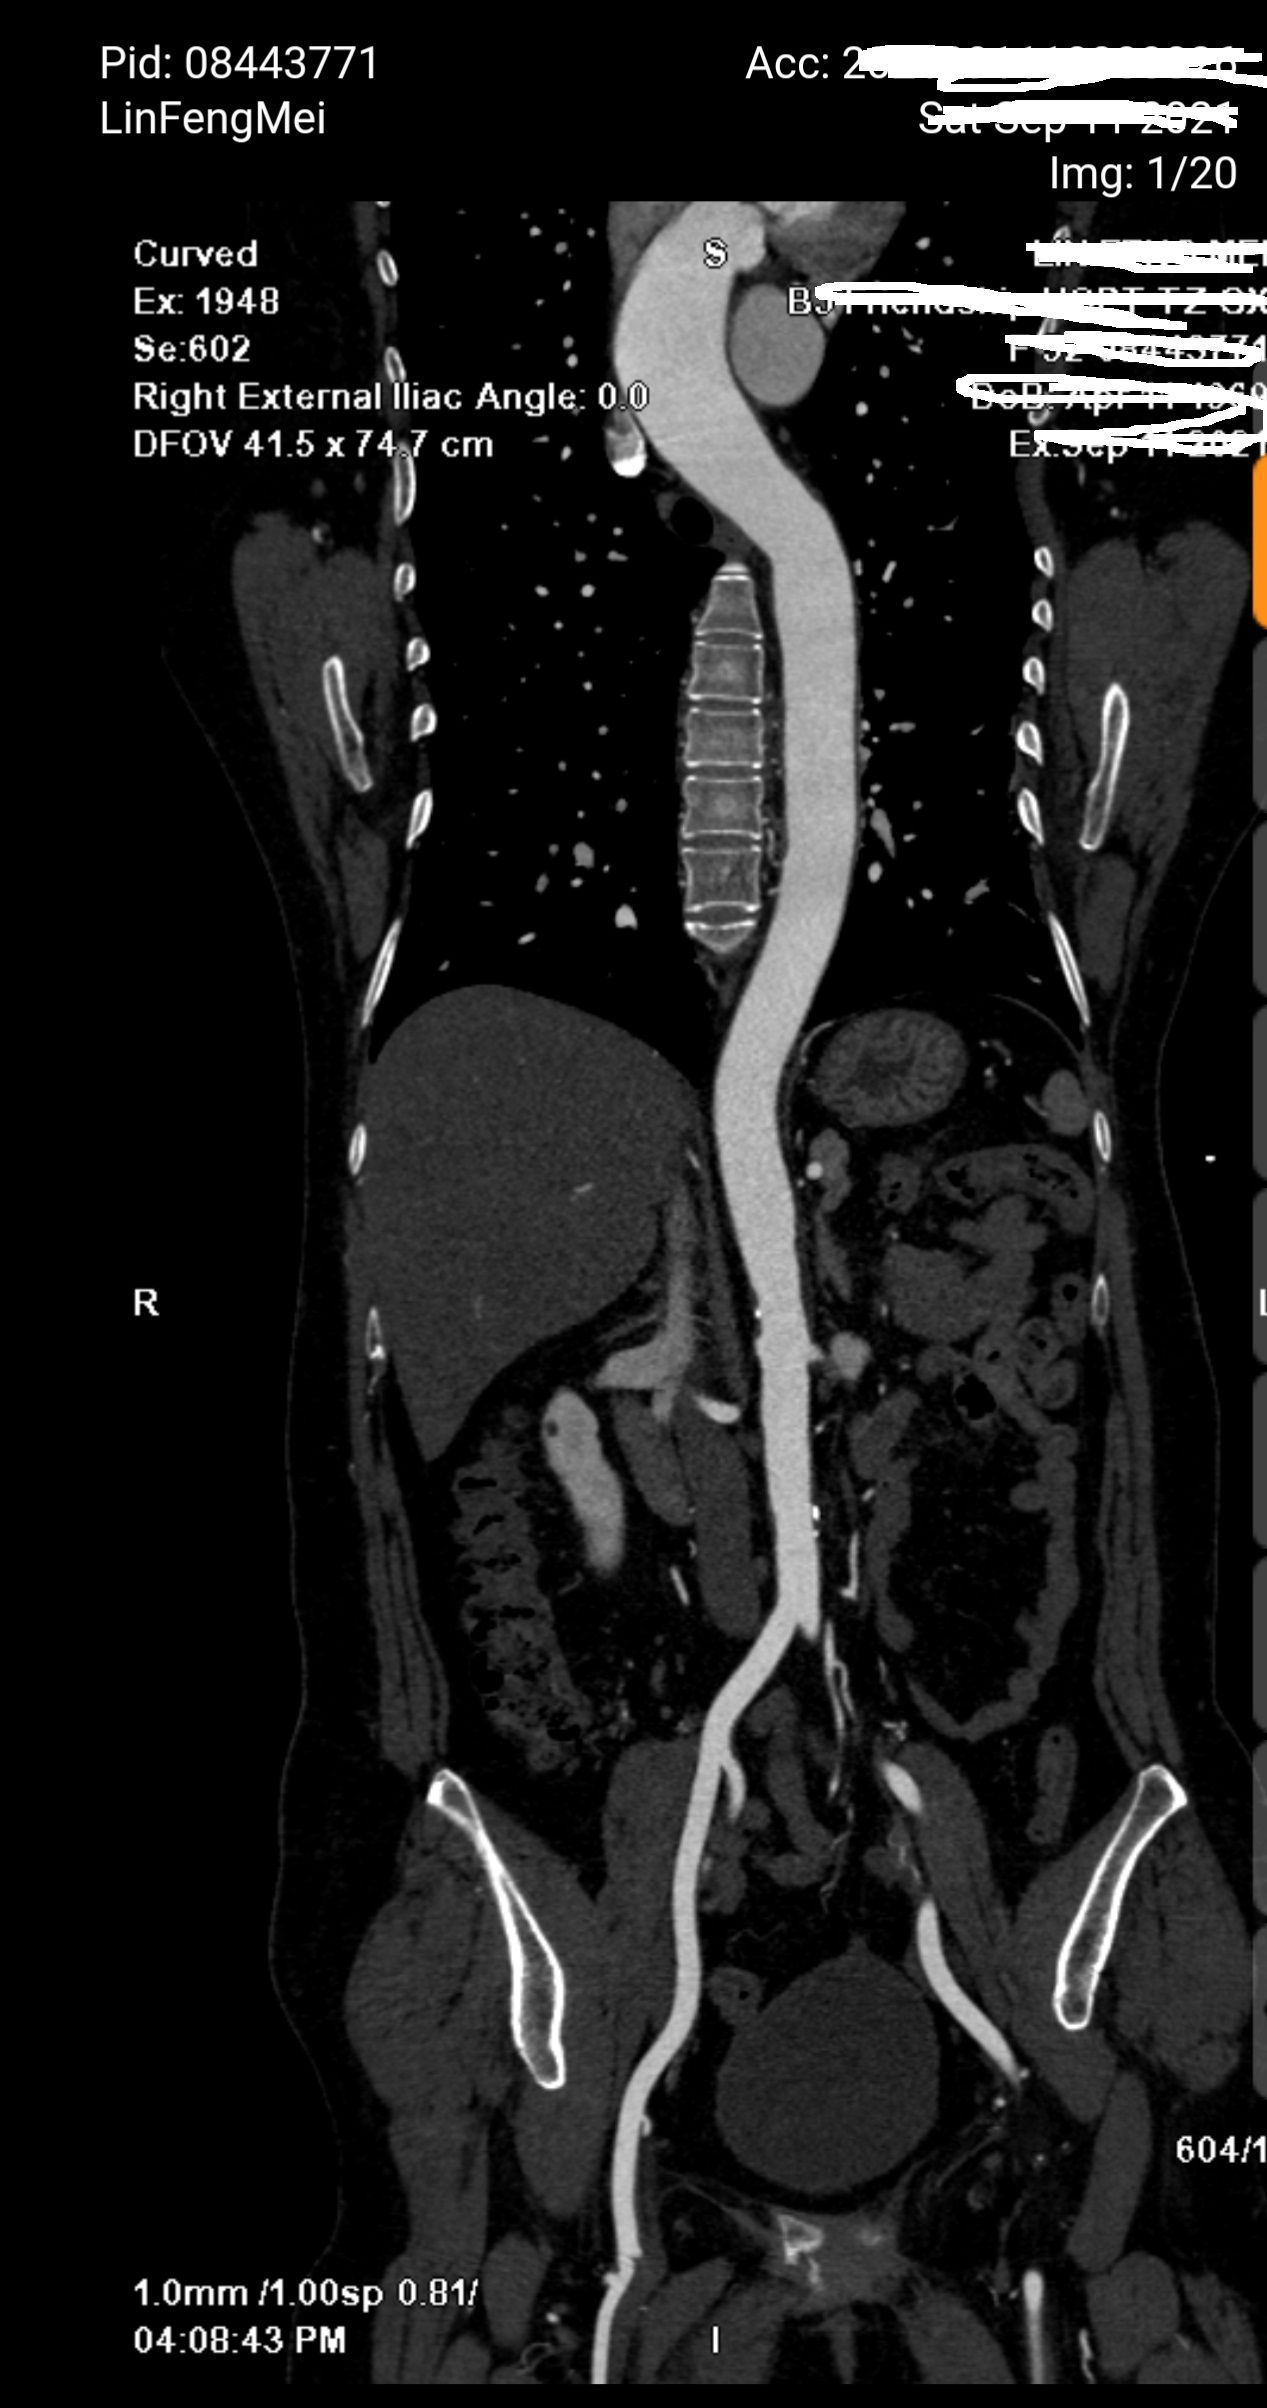

因为血压严重升高,马上开始降压治疗,并联系心内科。患者症状和心电图虽然符合急性心梗表现,但是考虑严重高血压(双侧基本一致),胸痛剧烈,还是马上安排了一个主动脉CTA,排除一下主动脉夹层,因为这也是要命的疾病,而且和急性心梗治疗刚好相悖。幸运的是患者CTA正常,排除了夹层。

主动脉CTA